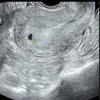

Kebahagiaan tengah menyelimuti hati Amanda Manopo dan Kenny Austin. Ya, Amanda mengumumkan dirinya hamil anak pertama pada Selasa (25/11) lewat Instagram pribadinya.

Ia dan suami tampak senang memamerkan hasil test pack yang menunjukkan positif hamil. Berikut selengkapnya.